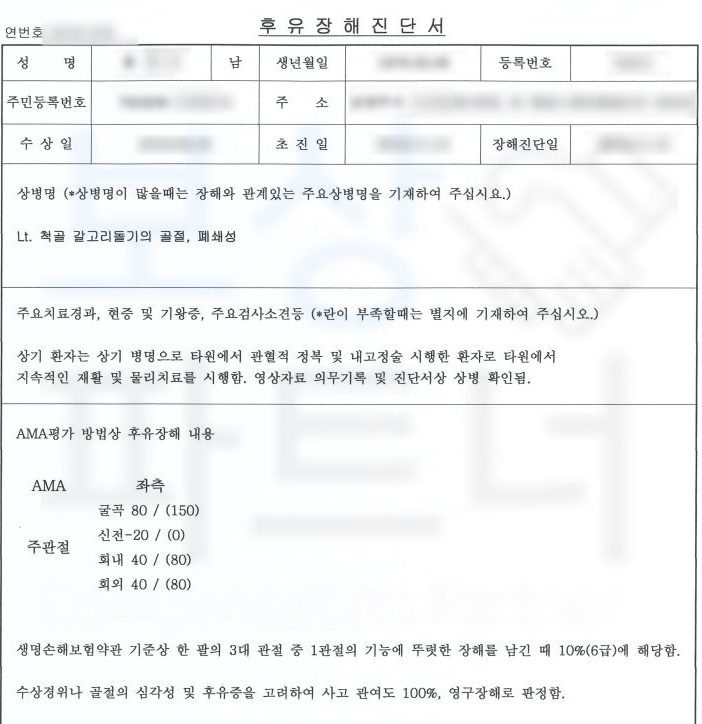

보상파트너는 유@@님의 장해약관에 근거한 올바르고 객관적인 장해평가를 위해 공신력있는 대학병원의 전문의로부터 후유장해 평가를 의뢰했고 그 결과,

주관절의 뚜렷한 기능장해 10% 6급에 해당하였습니다. 물론 위 진단서를 기초로 각 보험사에 청구하였지만 조사관이 배정되어 내부 의료자문도 해야했습니다. 하지만 보상파트너는

청구한 지급율 10% 모두 인정받아

후유장해보험금 550만원

지급받을 수 있었습니다. 팔꿈치골절 후유장해 보상은 약관에 근거한 객관적인 장해평가와 보험사의 분쟁 유도에 적절한 대응이 필요합니다. 따라서 보상 전.문.가 에게 문의하실 때 확실한 보상 기대하실 수 있겠죠.